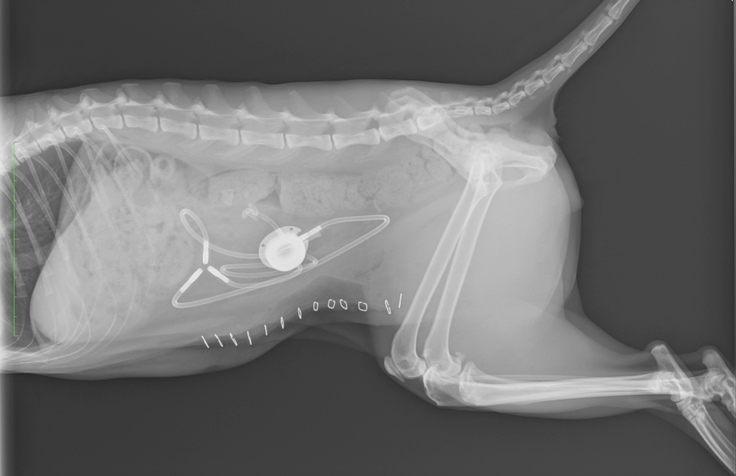

手術後のお腹の中はどうなっているのかな?と

気になったので写真を頂いてみました!

医療技術の進歩は凄いですね‼️

今後はSUBシステムのポート洗浄を

行う必要があります!